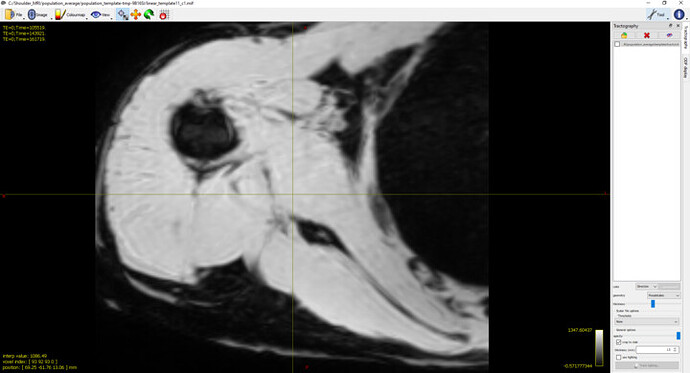

What I’ve Tried: To explore this further, I conducted two sets of tests with identical settings for rigid and affine registrations.The averaged mdixon images after rigid and affine registration appear satisfactory (refer to screenshot 1) :